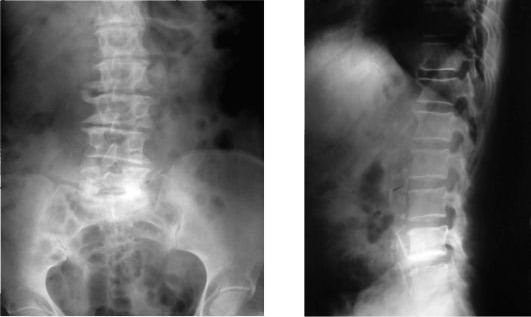

Опытный специалист может установить диагноз, основываясь на жалобах пациента и проявляющихся симптомах. Главным методом диагностики является рентгенография позвоночника, которая выполняется в трех проекциях. Перед рентгеном необходимо очистить кишечник с помощью клизмы. На снимках четко видны остеофиты. Процесс их развития делится на несколько стадий:

- Первая стадия — наблюдаются многочисленные патологические наросты на позвонках, межпозвонковые диски остаются неизменными и находятся в норме.

- Вторая стадия — остеофиты выходят за пределы позвонков; их количество значительно увеличивается. Некоторые остеофиты могут соединяться, формируя новый сустав.

- Третья стадия — происходит сращение остеофитов нескольких позвонков.

Также наблюдается отслоение передней продольной связки от позвонков. В процессе диагностики применяются компьютерная томография (КТ) и магнитно-резонансная томография (МРТ), которые предоставляют более детальную информацию, позволяя изучать состояние позвоночника послойно. Это дает возможность визуализировать состояние межпозвонковых дисков, мышц и связок. Даже незначительные остеофиты не останутся незамеченными. Лабораторные анализы в данном случае не играют значительной роли в диагностике.